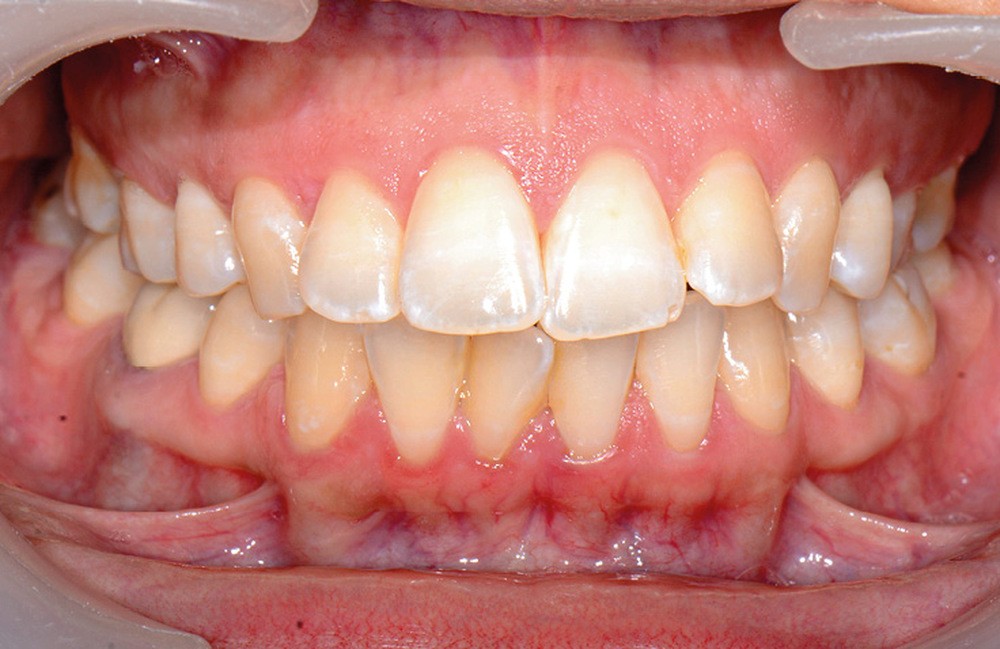

C’est précisément le cas de cette patiente de 33 ans qui présente une classe II squelettique par rétrognathie mandibulaire sur un schéma vertical hyperdivergent associée à une classe II/1 dentaire avec DDA par excès et biproalvéolie. Son profil est convexe, cis-frontal et, sur le plan fonctionnel, on peut observer une dysfonction linguale et une incompétence labiale au repos. Il en résulte une contracture des muscles de la sphère péri-orale lèvres jointes. La formule dentaire n’est pas complète puisque les quatre deuxièmes prémolaires ont été extraites lors d’un premier traitement orthodontique et qu’il y a également agénésie des troisièmes molaires 18 et 38 (fig 1 à 11).